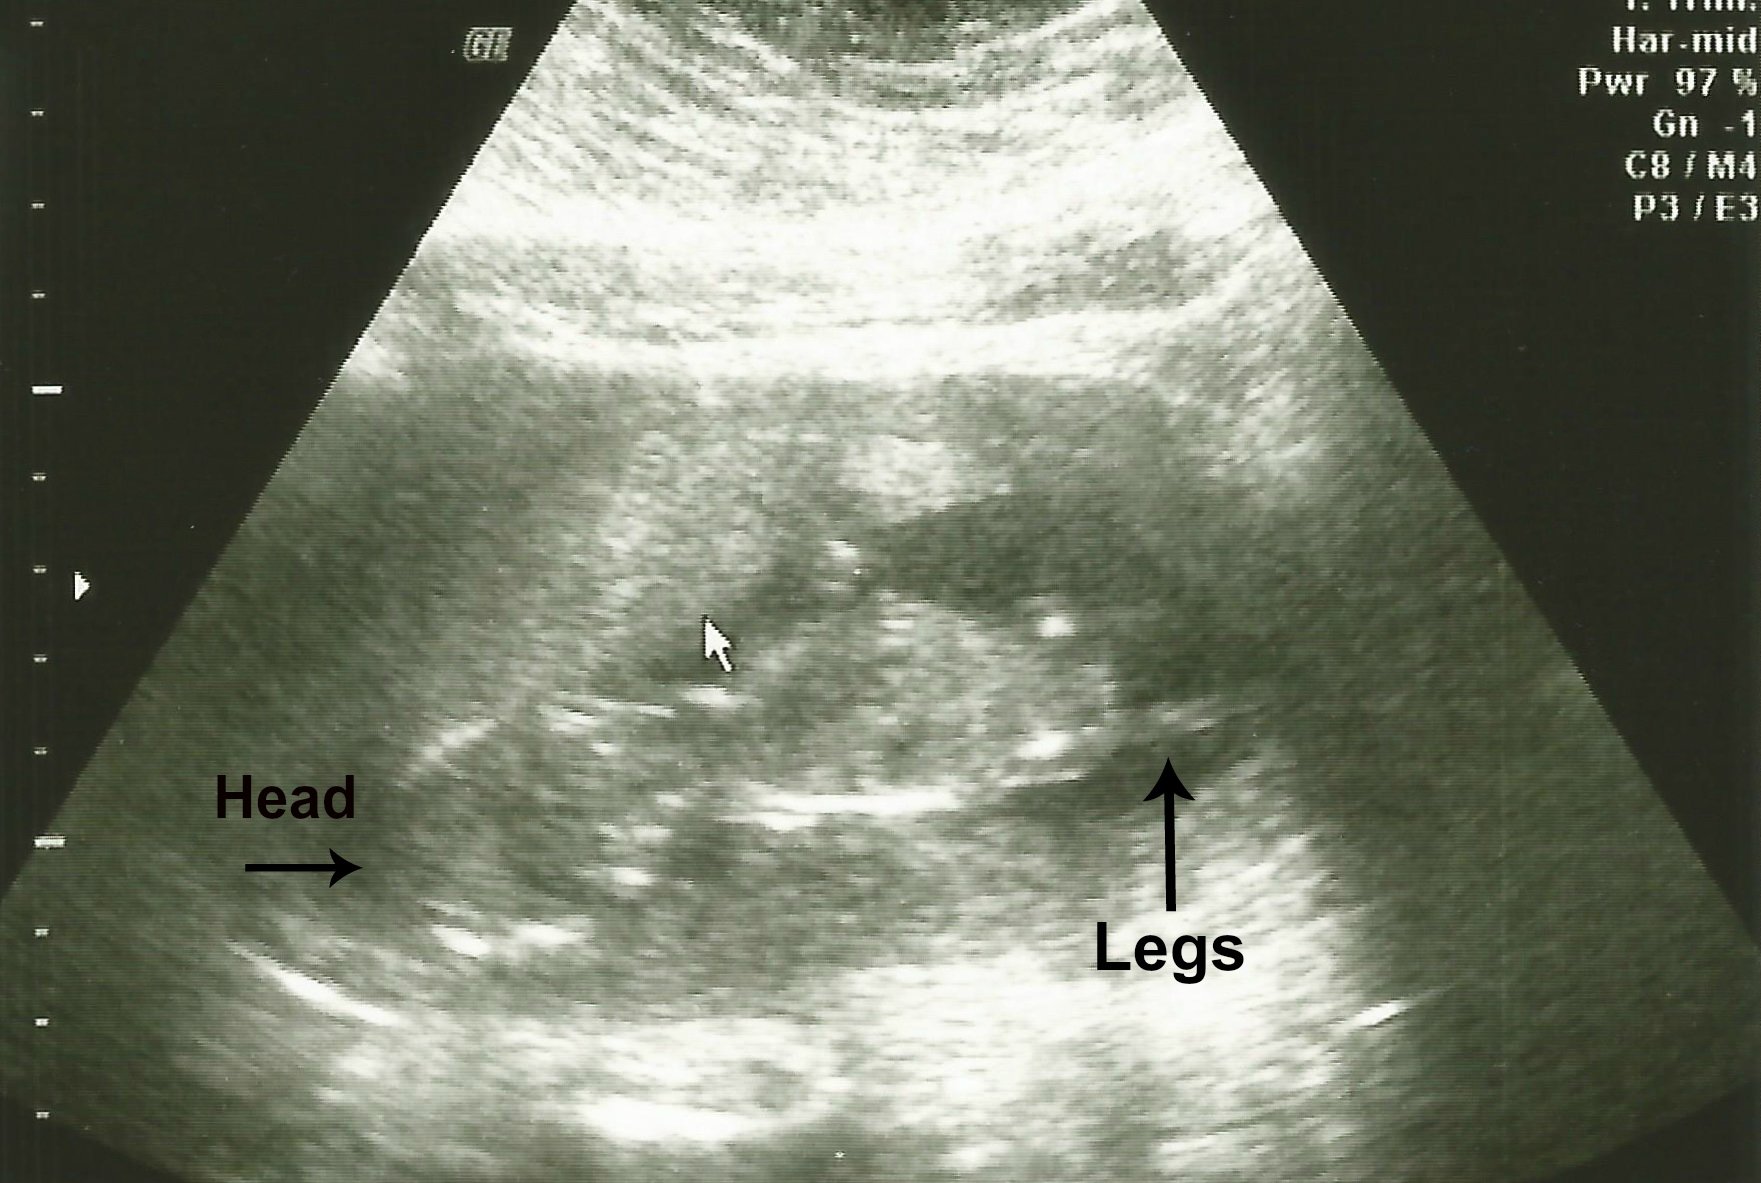

My Ultrasound from today:

I went for my 13 week ultrasound today, and the tech said that the baby is bigger & instead of July 8th as my due date, she said it was closer to June 30-July 4. My name is Sherry & I'm 41 years old, this is my first pregnancy.   You heard that right... I'm 41 & this is my first pregnancy.

Then he talked to my husband & I for a little bit.  I was scheduled to do a genetic test called EARLY SCREEN, it includes an ultrasound & blood work.  The ultrasound showed me being 14 weeks, not 13 weeks - so they couldn't do the blood work.  But the Dr said the ultrasound you measure the skin on the back of the neck, and that looked normal.  He said he didn't think we needed to do any other testing unless we wanted to.  DH & I had already researched & decided that we didn't want any other testing.  He said that everything looked great, and he believes that we will have a normal pregnancy.  My due date is somewhere between June 30-July 3.  He gave me a due date of July 3, but was pretty certain that it would be before July even got here.  He calmed all my fears about being 41 & even made us laugh a few times.... it was pretty awesome.